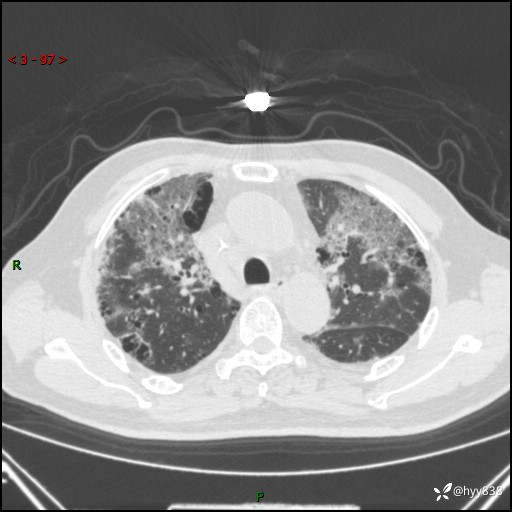

患者性别:男

患者年龄:64岁

简要病史:肝内胆管癌综合治疗后2周余,咳嗽、发热,咳白色泡沫痰。

辅助检查:CT

临床诊断:感染?

讨论:病变性质?